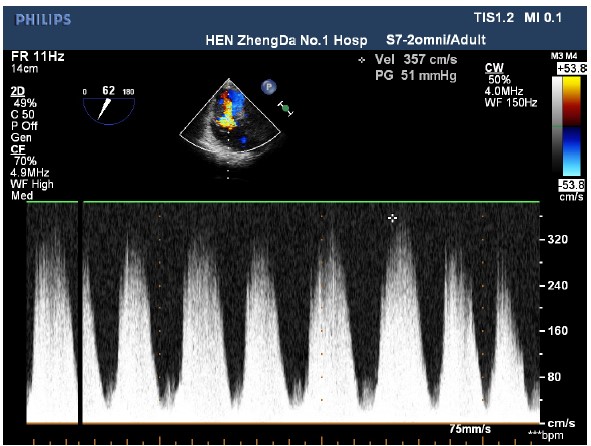

The patient entered the operating room and her ECG was monitored regularly. The induction of anesthesia was smooth. When the surgical team was manipulating the fracture, her blood pressure (BP) suddenly decreased to 63/43 mmHg, heart rate increased to 112 beats/min, and the saturation of pulse oxygen (SpO2) fell to 72%. 1 mg methoxamine was used to raise the blood pressure without success. 2 mg methoxamine, 6 mg ephedrine, and 8 μg nonadrenaline were subsequently given without significant blood pressure change. The central venous pressure was 15mmHg. In addition, the end tidal carbon dioxide decreased to 10 mmHg. There were no significant airway pressure changes. While an allergic reaction was initially suspected, no dermatological changes were identified. Emergency blood gas indicated a partial pressure of artery carbon dioxide (PaCO2) of 77.9 mmHg, and an oxygen partial pressure of 67mmHg. Potential pulmonary embolism was suspected. A transesophageal echocardiography (TEE) was followed. It revealed an enlarged right atrium (Figure1), hypokinesia of the free right ventricle wall, and poor filling of left ventricular. The ratio of left/right ventricular apparent disorder and the pressure of tricuspid valve was 51mmHg with massive regurgitation of 3.57m/s (Figure 2). Severe tricuspid reflux was also observed (Figure 3). Epinephrine and milrinone along with high-dose vasopressin were initiated. While no thrombi in the pulmonary or right ventricle were identified, unstable hemodynamics, changes in carbon dioxide, findings in TEE strongly suggested a possible major PE. Extracorporeal membrane oxygenation (ECMO) was immediately established and an emergent pulmonary thromboembolectomy was successfully performed. The patient was transferred to the surgical intensive care unit for monitoring and evaluation. The patient was discharged without residual deficits after 20 days in surgical intensive care unit.

Figure 2: An imaging of a 2D-transesophageal echocardiography shows tricuspid valve regurgitation with the speed of 3.57m/s and Tricuspid valve pressure of 51 mmHg.